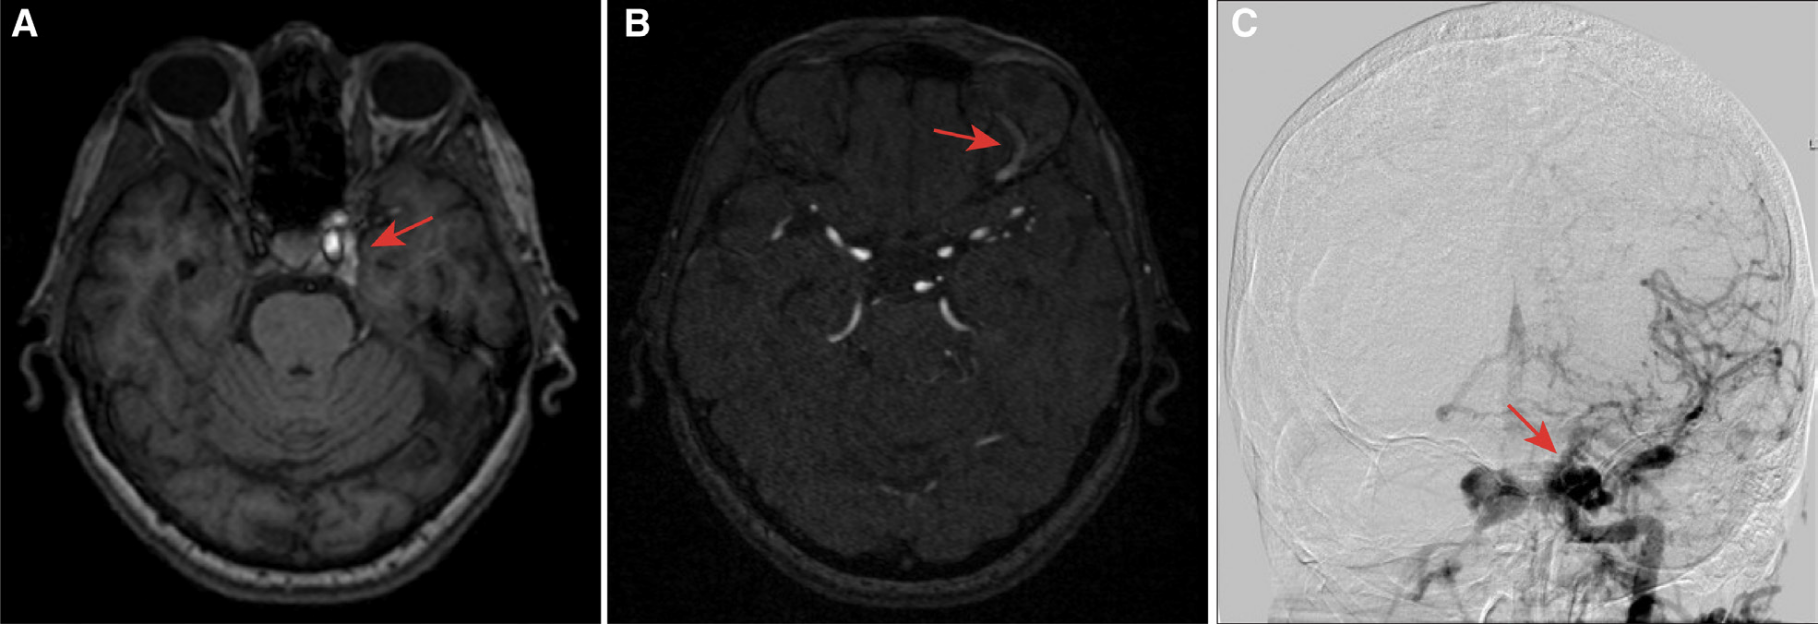

10天后,患者因头痛复发、复视加重及左眼肿胀再次来院就诊。再次查体发现患者左眼周围红肿,双眼外展受限,左侧较右侧严重,提示双侧外展神经受损。遮盖-不遮盖试验提示双侧内斜视。头部MRA和MRV显示左侧海绵窦不对称强化,左侧眼上静脉扩张,提示颈动脉-海绵窦瘘(CCF),但没有静脉窦血栓形成(图1)。DSA证实了CCF,为颈内动脉海绵窦段动脉瘤破裂所致。患者接受了血管内治疗:(1)左侧颈内动脉海绵窦段分流器支架置入 (2)经静脉弹簧圈栓塞瘘口(图2)。

图1 MRA提示颈内动脉海绵窦瘘(CCF),A:左侧海绵窦不对称强化,B:左侧眼上静脉扩张,C:DSA提示CCF位于左侧颈内动脉,同时可见左侧海绵窦通过海绵间窦使右侧海绵窦早期显影。